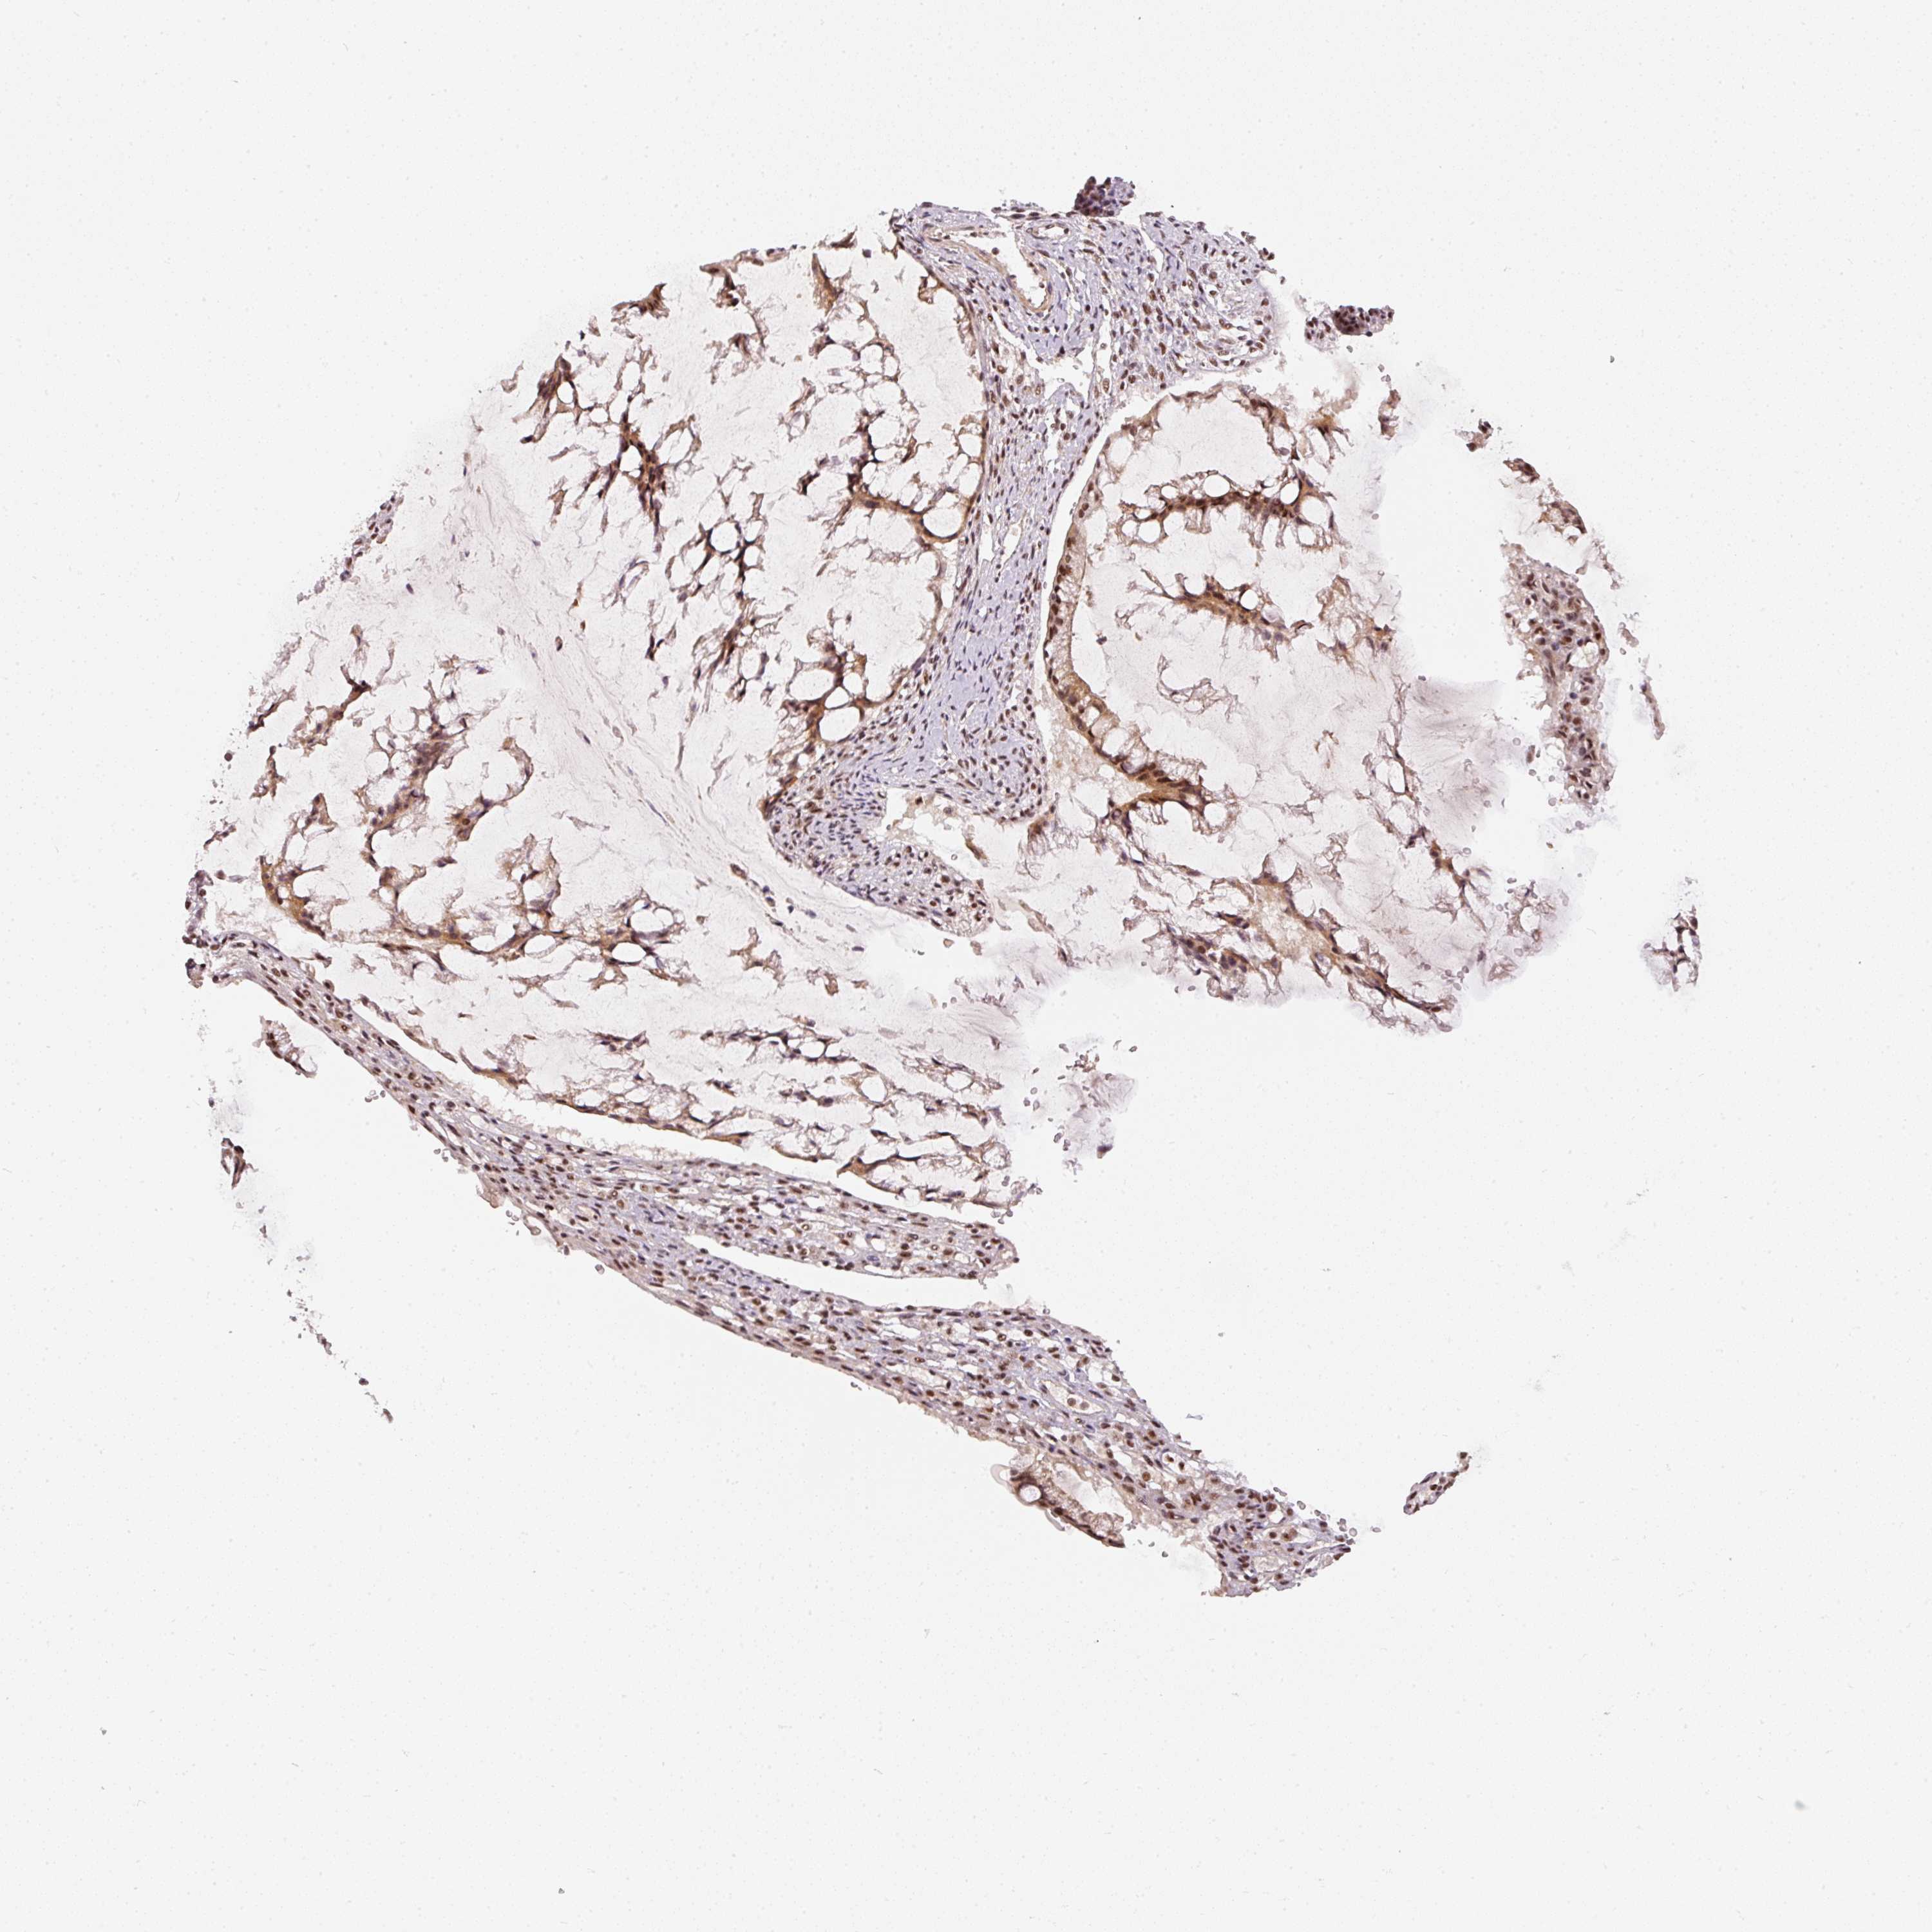

OVARIAN CANCER - Protein expressioni

A mouse-over function shows sample information and annotation data. Click on an image to view it in a full screen mode. Samples can be filtered based on level of antibody staining by selecting one or several of the following categories: high, medium, low and not detected. The assay and annotation is described here.

Note that samples used for immunohistochemistry by the Human Protein Atlas do not correspond to samples in the TCGA dataset.

Antibody stainingi

Antibody staining in the annotated cell types in the current human tissue is reported as not detected, low, medium, or high, based on conventional immunohistochemistry profiling in selected tissues. This score is based on the combination of the staining intensity and fraction of stained cells.

Each image is clickable and will lead to virtual microscopy that enables deeper exploration of all samples and also displays staining intensity scores, fraction scores and subcellular localization as well as patient and tissue information for each sample.

Antibody HPA052953

Staining

High

Medium

Low

Not detected

Intensity

Strong

Moderate

Weak

Negative

Quantity

>75%

75%-25%

<25%

None

Location

Nuclear

Cytoplasmic/membranous

Cytoplasmic/membranous,nuclear

Cystadenocarcinoma, serous, NOS

Carcinoma, endometroid

Cystadenocarcinoma, mucinous, NOS

Carcinoma, NOS